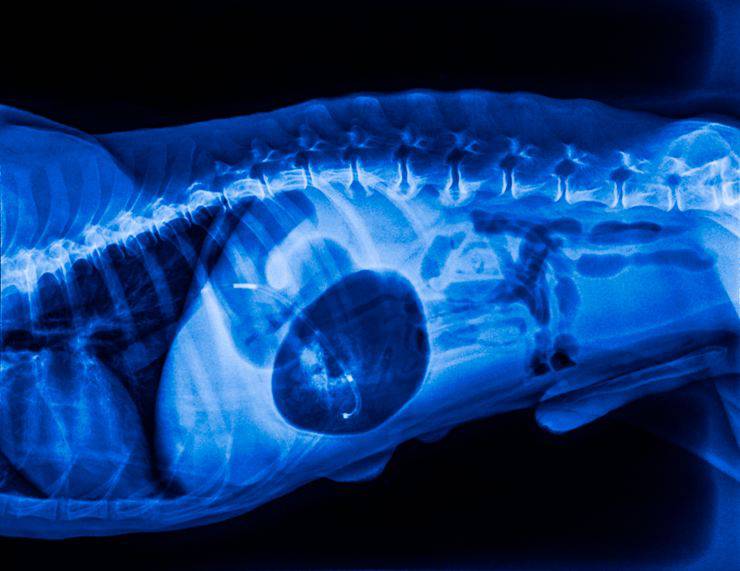

Si tratta di una condizione dello stomaco che, in seguito a determinati fattori scatenanti, si gonfia in modo sproporzionato e si rigira su se stesso. La forma che andrà ad assumere è simile ad un sacco che, naturalmente, va ad occupare uno spazio ancora maggiore all’interno dello stomaco. I gas interni aumenteranno e la circolazione del sangue si bloccherà: quindi gli organi potrebbero andare incontro a necrosi. Se non ci accorgiamo in tempo di questi sintomi il cane potrebbe morire in breve tempo.

Dilatandosi, lo stomaco produce più gas; ma se si parla di torsione gastrica significa che esso ha già iniziato a rigirarsi su sé stesso. Non sarà concesso perdere tempo, ed è importante notare i primi segnali che ci invia il nostro amato Fido.

Si tratta di un intervento chirurgico che ‘fissa’ le pareti dello stomaco alle costole del cane. Quindi, anche se dovesse dilatarsi, questo organo non riuscirebbe mai a torcersi su sé stesso. L’operazione si effettua in laparoscopia, quindi è minimamente invasiva poiché si effettua attraverso due fori sul fianco del cane. Non è né particolarmente dolorosa al momento né nel post-operatorio: infatti bisognerà fare attenzione che la ferita si cicatrizzi per bene e non faccia infezione.